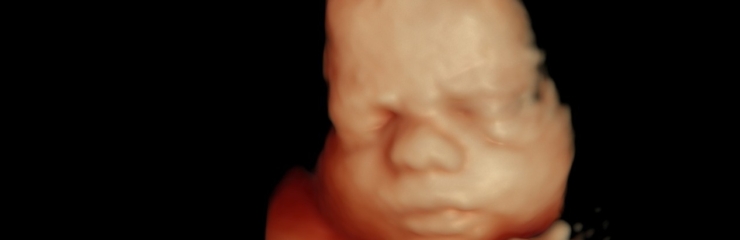

Loode:

Loode võib olla võtnud sisse pea alaspidi asendi. Süda lööb umbes

120-160 lööki minutis. Loode võib aeg-ajalt luksuda. Loote nahk on nüüd roosa. Loode eristab valgust ja pimedust ning kaalub umbes 2,2 kilogrammi. 35. nädalal kaalub loode umbes 2,5 kilogrammi. 36. nädalal on loode täiesti välja arenenud. Ta on umbes 45 sentimeetri pikkune. Pea läbimõõt on umbes 9 sentimeetrit.

Uuringud:

Loote eesasuva osa määramine (tuharseis) Ultraheliuuringu vajadust hindab arst, ultraheliuuring võimaldab hinnata loote oletavat kaalu, lootevee hulka, platsenta asukohta ja loote seisu, hoiakut, asetsust ja eesasuvat osa, visualiseerida loote strukturaalseid anomaaliad.

Uriinianalüüs

Vajadusel vereanalüüsid

Loote liigutuste jälgimine ja loote südamelöökide kuulatlemine Vajadusel kardiotokograafia